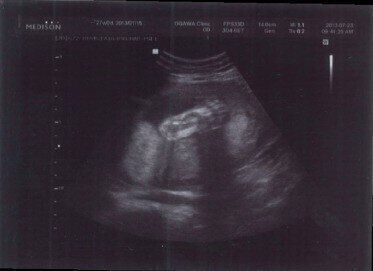

骨や内臓などがわかる!診断のために必要な2D超音波

一般的な超音波写真は、この2D超音波。赤ちゃんを立体的にとらえるのではなく、体の断面を映し出し、骨や内臓などの状態を観察するのが目的です。

断面の画像なので、初めて見るときはどの部分かよくわからないかもしれませんが、背骨の位置がわかると見当がつくようになります。